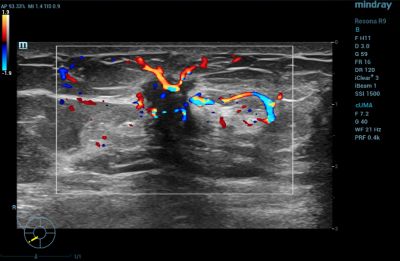

Thyroid

CDI is routinely used in thyroid gland imaging to further classify and aid in diagnosing thyroid lesions.

Power Doppler Imaging of Thyroid Lesion